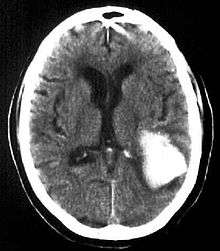

| Multiple intraparenchymal hemorrhage | |

Intraparenchymal hemorrhage (IPH) is one form of intracerebral bleeding in which there is bleeding within brain parenchyma. The other form is intraventricular hemorrhage (IVH).

Intraparenchymal hemorrhage accounts for approx. 8-13% of all strokes and results from a wide spectrum of disorders. It is more likely to result in death or major disability than ischemic stroke or subarachnoid hemorrhage, and therefore constitutes an immediate medical emergency. Intracerebral hemorrhages and accompanying edema may disrupt or compress adjacent brain tissue, leading to neurological dysfunction. Substantial displacement of brain parenchyma may cause elevation of intracranial pressure (ICP) and potentially fatal herniation syndromes.